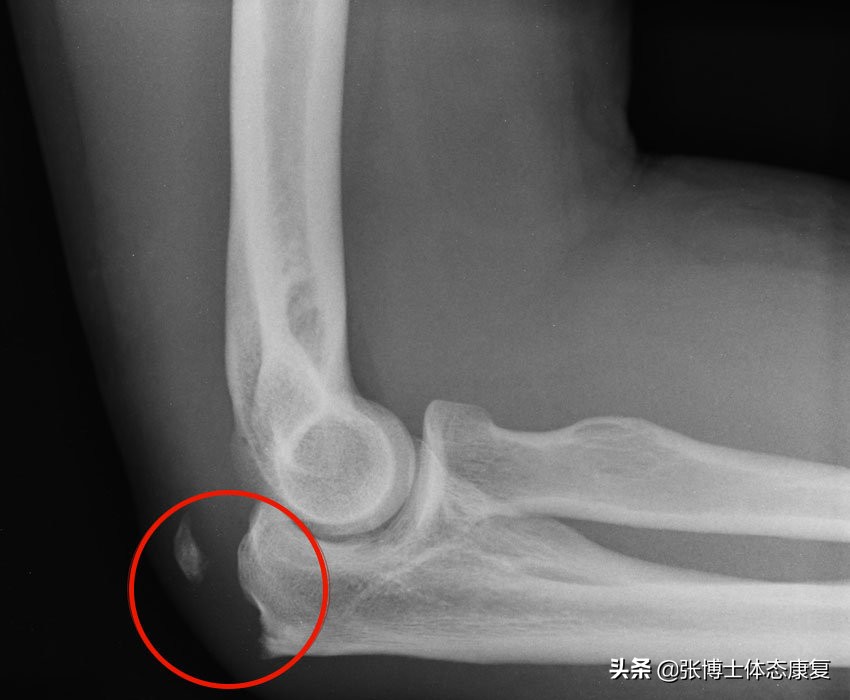

2.尺骨鹰嘴骨折

是指肘后部的大块骨的骨折(称为鹰嘴骨折)。它通常是由于直接撞击或摔倒时肘部屈曲断裂造成的。